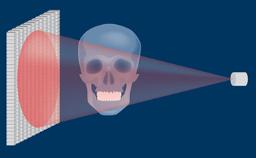

O uso de implantes dentários tornou-se um tratamento padrão em muitas situações clínicas. No entanto, para alcançar resultados funcionais e estéticos ideais, o clínico deve avaliar a complexidade e os riscos associados a uma terapia de implante antes de iniciar o tratamento. O sistema de classificação SAC diferencia entre tratamentos simples, avançados e complexos. A 2ª Edição totalmente revisada da Classificação SAC em Implantodontia foi atualizada para garantir consistência com a prática contemporânea de implantes. A nova versão do SAC Assessment Tool também está disponível aqui.

- descrever os determinantes da Classificação SAC

- descrever o processo usado para desenvolver uma classificação